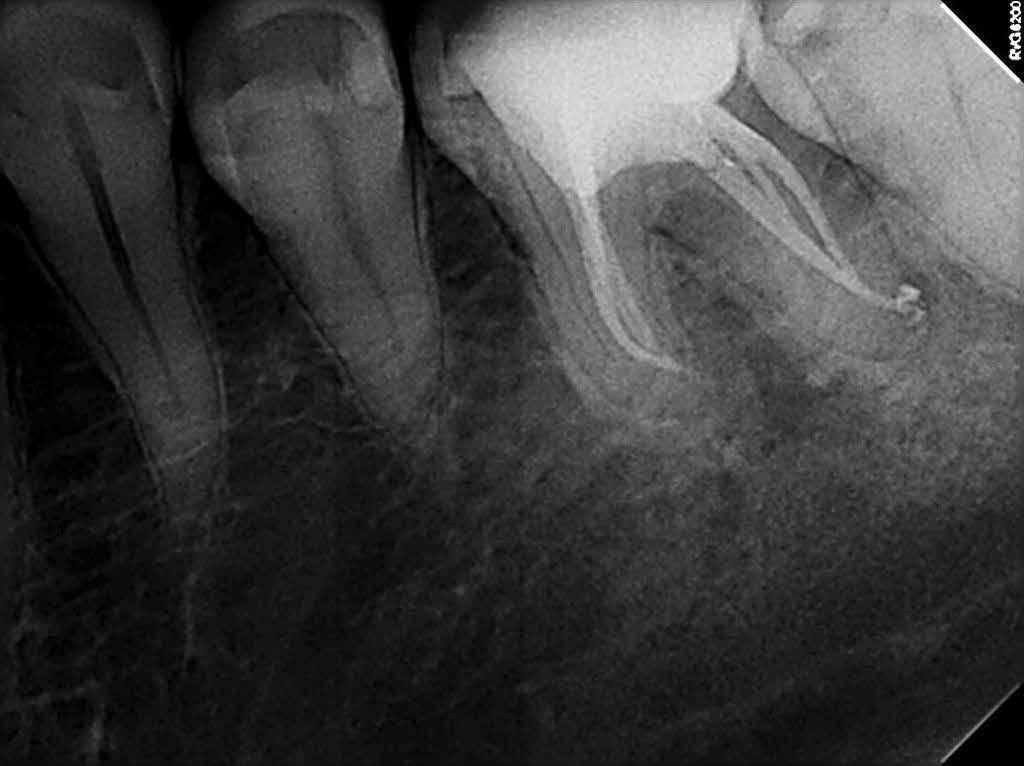

A kezdeti konzultáció során az LL6 nem reagált az Endo-Frost (COLTENE) és az Electric Pulp testerrel végzett érzékenységi vizsgálatokra, és ütögetésre érzékenynek bizonyult. Bukkálisan a lágyrészekhez kapcsolódó fisztulát észleltek, és tapintásra némi érzékenységet, míg a fogak mozgékonysága a normális határokon belül volt. A műtét előtt készült periapikális röntgenfelvételen az LL6 gyökereihez kapcsolódó periradikuláris röntgenfelvételek voltak láthatóak (1. ábra).

Ebben az esetben hat csatornát azonosítottak és kezeltek. Általában az alsó állkapocs első őrlőfogainak három-négy csatornája van.[i] Azt is feltételezték, hogy az első alsó őrlőfogak 3%-ának lehet egy harmadik meziális vagy disztális csatornája.[ii] Ebben az esetben egy harmadik csatornát azonosítottak és kezeltek mind meziálisan, mind disztálisan, és az utóbbi lelet előfordulása egyetlen fogban rendkívül ritka, mindössze három esetről szóló közlemény jelent meg [iii], [iv], [v].

Az LL6 végleges obturálását folyamatos kondenzációs hullámtechnikával végeztük, és a hozzáférési üreget a COLTENE által gyártott, több árnyalatú nano hibrid kompozittal, aMIRIS®2-vel zártuk le (2–4. ábra).